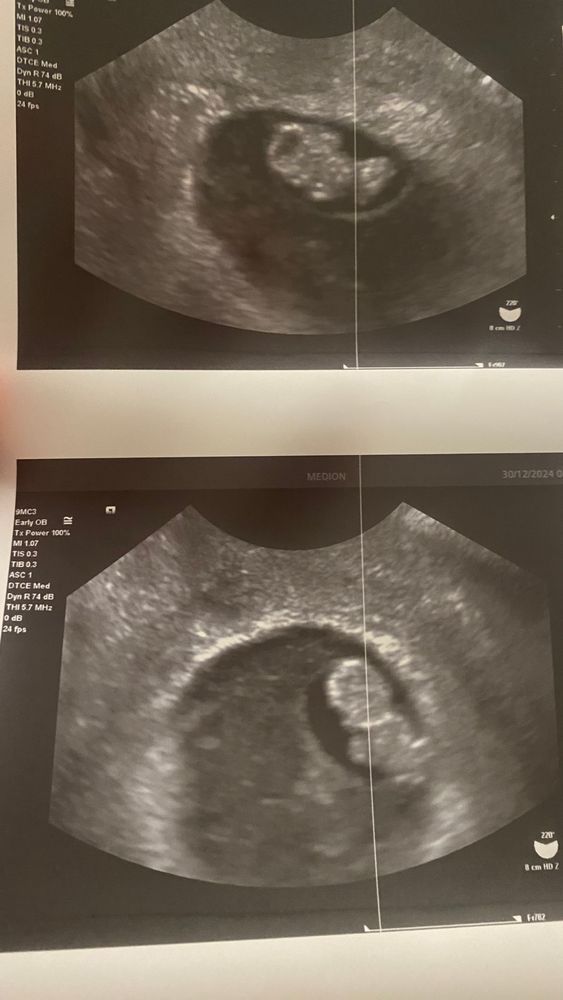

Счастливый день🥳узи 8 недель 2 дня

УЗИ, КТГ, доплерШла на узи,ожидая увидеть пельмень! А там! А там пупсик уже,который дергает ногами😨 я обалдела и умилилась,когда мужу показывали малыша,у него такой взглад растерянный и счастливый был😌

По узи срок день в день с М. Ктр-17,5мм

пя-40,1мм

жм-4,6мм

чсс 144 уд/мин